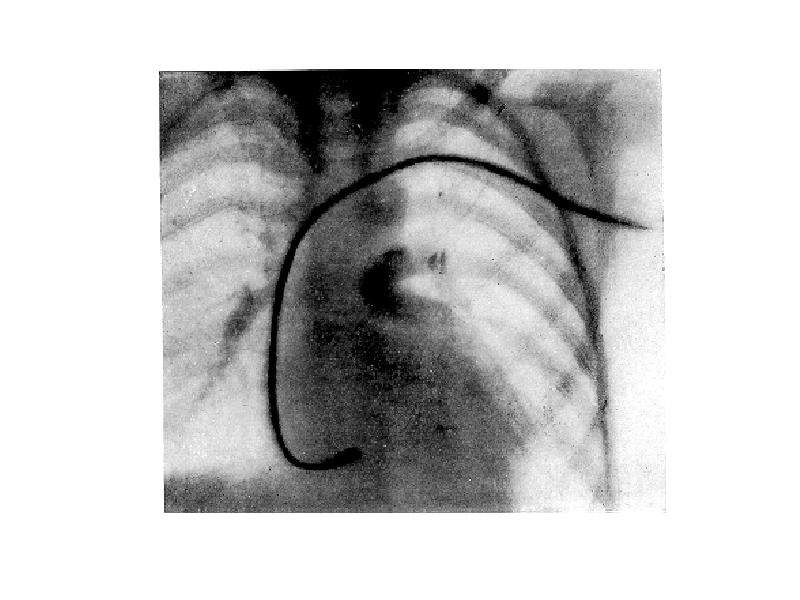

Дифференциальная диагностика заболеваний плевры